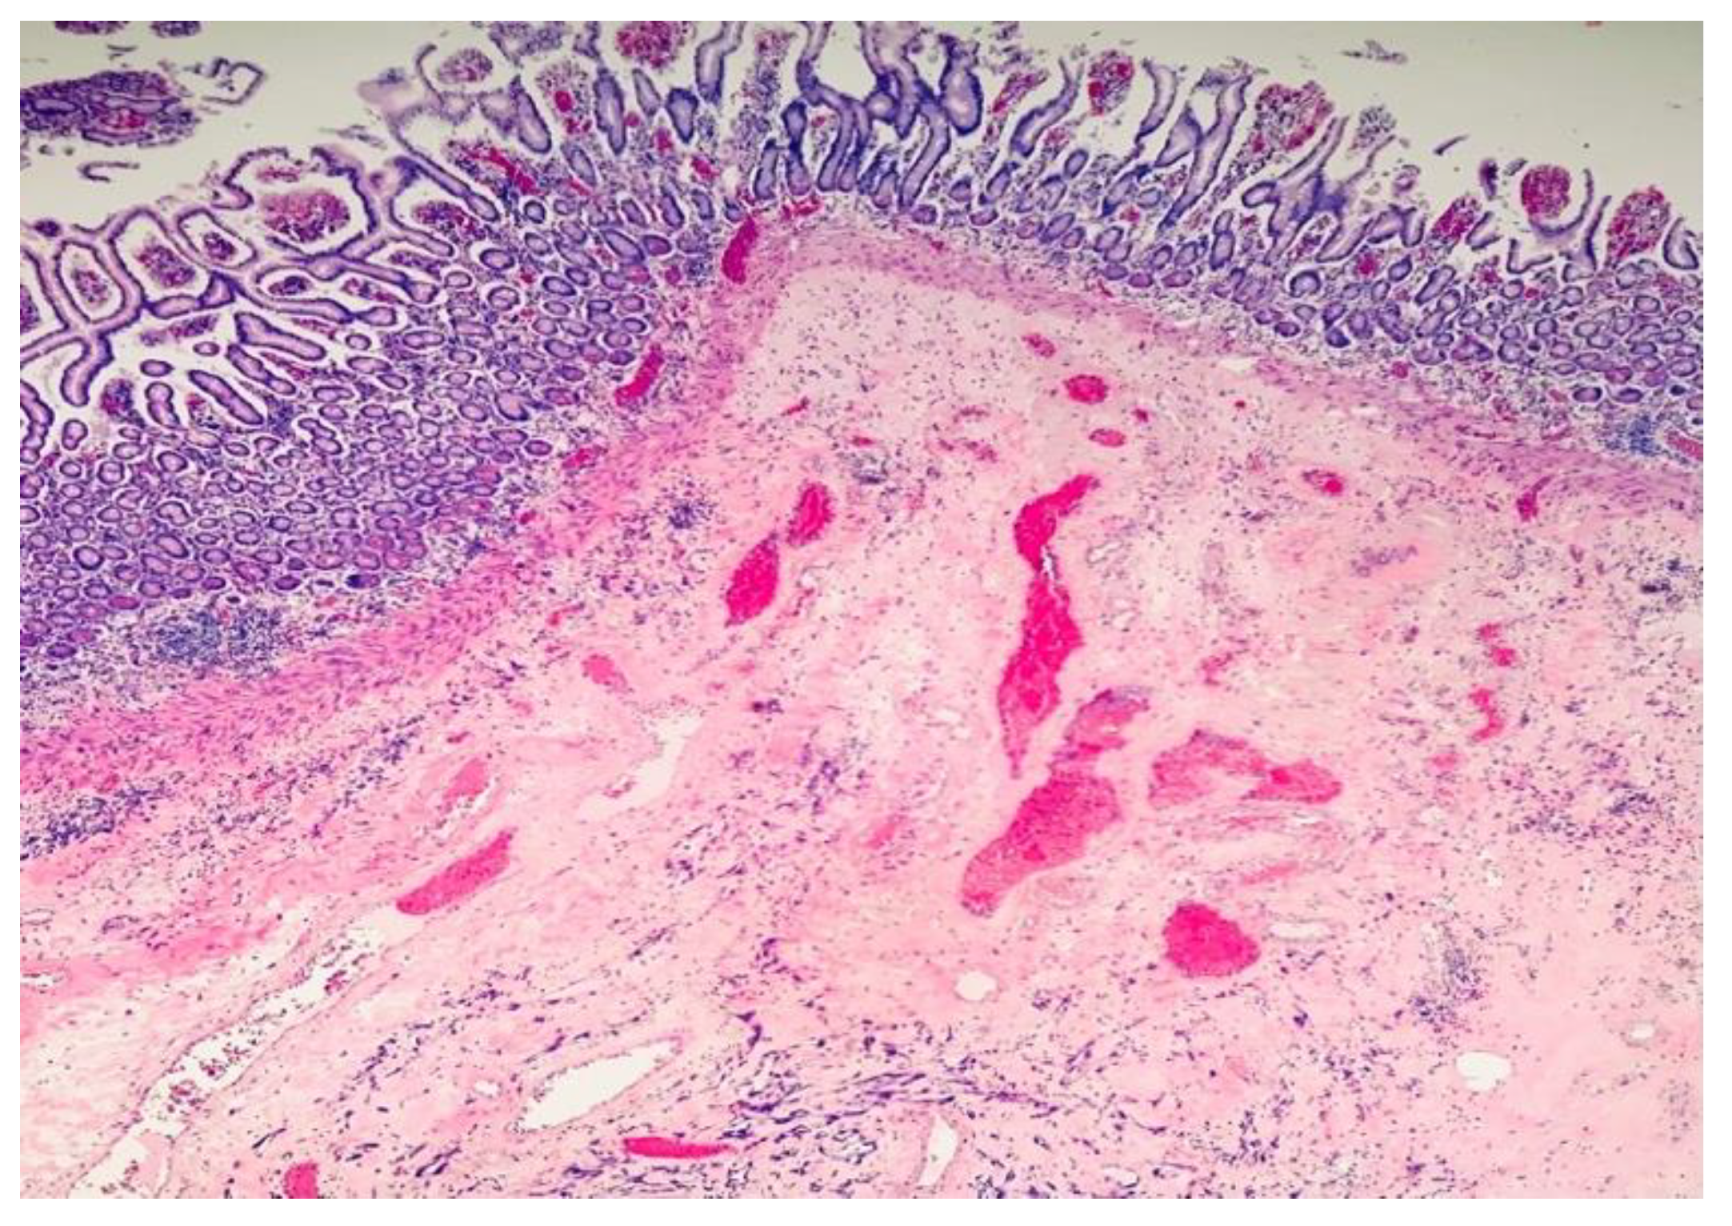

2. Case Report and Evolution